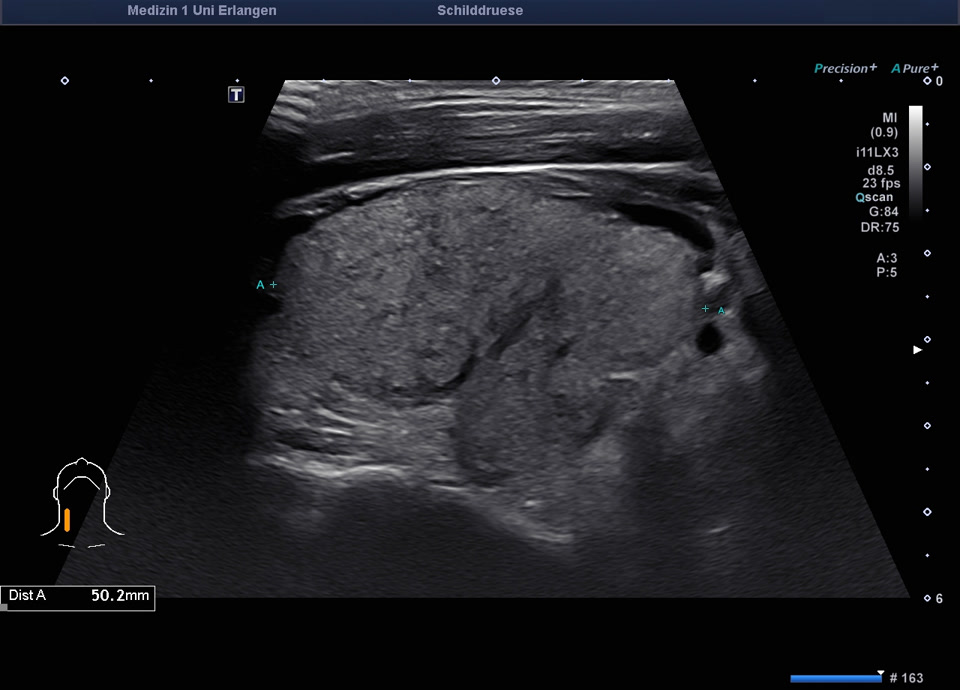

45-year-old male presented patient with persistent sore throat and general symptoms following an EBV-infection. An external diagnosis of post-infectious de Quervain’s thyroiditis had already been made, and a two-week course of corticosteroid therapy was administered. Initial clinical improvement with reduced throat pain was noted under treatment, but symptoms reoccurred after discontinuation of corticosteroids. Laboratory findings revealed leukocytosis of 12,000/µl and CRP of 113 mg/l. Sonographically, a bilaterally enlarged thyroid gland with diffusely hypoechoic areas and inhomogeneous parenchyma was observed. Combined with the patient history, this was characteristic of a subacute thyroiditis with relapse after short-term corticosteroid therapy. Prolonged corticosteroid therapy with slow tapering was performed. Under this regimen, marked clinical improvement occurred within weeks; follow-up ultrasound four months later showed a normal-sized thyroid with only mildly inhomogeneous parenchyma, consistent with resolving thyroiditis.